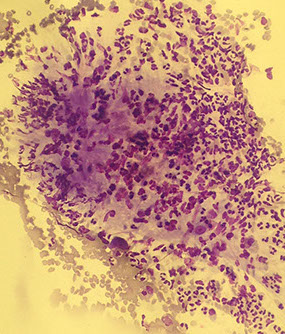

Adenoid Cystic Carcinoma (ACC)

Variably sized, often large , 3-D, acellular hyaline matrix globules and linear branching structures

Matrix is acellular with sharp borders (“cookie-cutter” like)

Basaloid cells

(Arrows show transparent hyaline globules on figure to left)